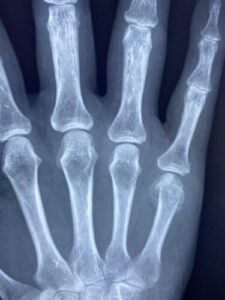

上肢の痛み・痺れ

牛久市で指の怪我(突き指・骨折・脱臼)にお悩みの方へ:症状の見分け方から…